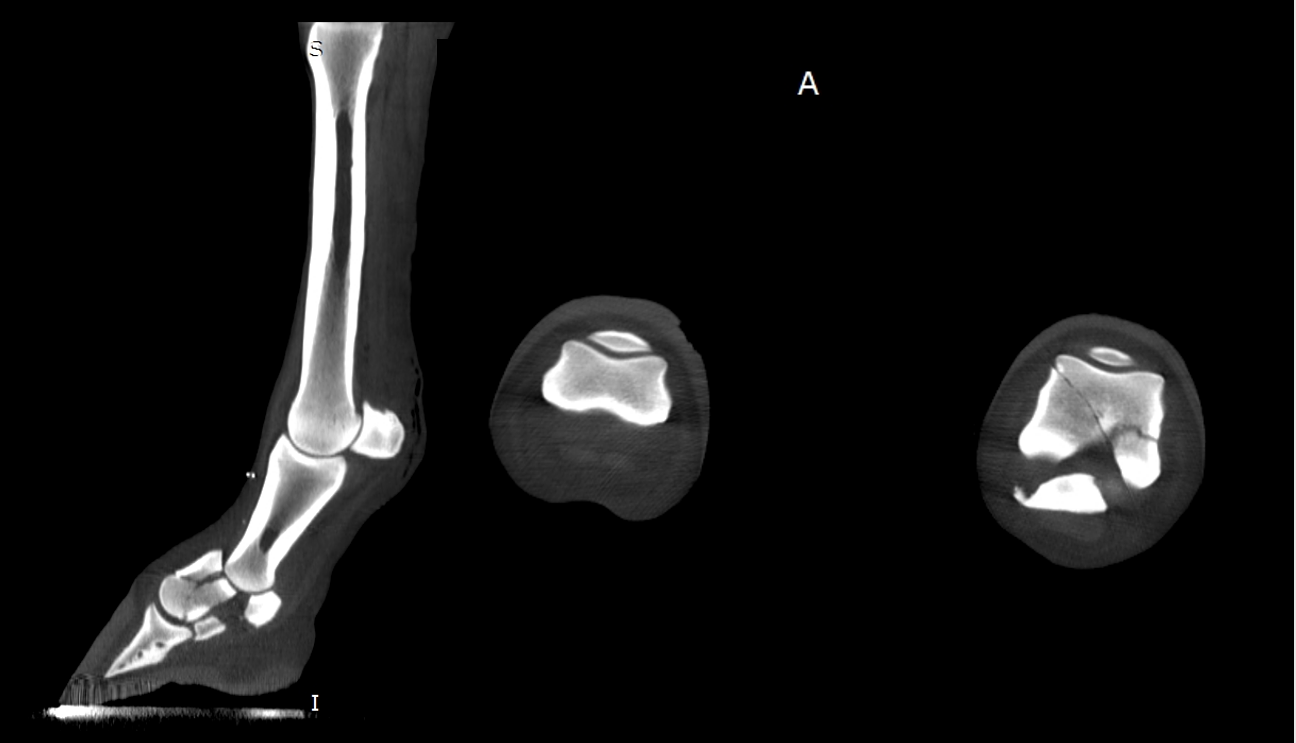

In the equine space, fan-beam systems offer several key advantages. Fan-beam systems offer faster scan times which make its images less susceptible to motion artifacts due to swaying or other subtle movements of the equine patient. Fan-beam images also have higher image quality, enabling them to be used to identify subtle pathological changes in the limbs of horses, and important advantage over both traditional radiography and cone-beam CT scanning.

The resulting Equina® system permits simultaneous imaging of both distal limbs in a weight-bearing stance. This enables assessment of anatomical structures under natural load, improving detection of subtle pathology.

Bones, joints, and soft tissues align differently when a horse is non-weight-bearing. Weight-bearing CT captures the structures as they function during movement and while bearing load, leading to more accurate diagnoses.